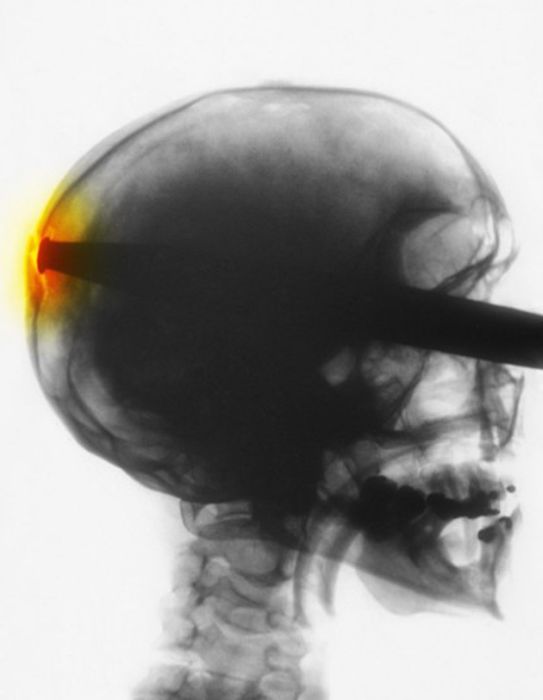

Рентгеновские снимки людей, которые умудрились сами или с чужой помощью разместить внутри своего организма разные посторонние предметы. От вилок и ножей до пуль и бензопилы (!!!). По этическим соображениям обычные снимки таких травм и повреждений выкладывать нельзя, зато рентгеновские можно – на них травмы видны достаточно условно, хоть и очень понятно.